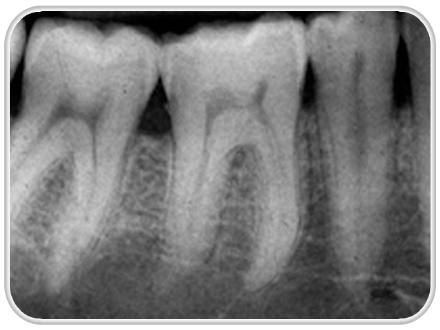

از رادیوگرافی اشعه ایکس برای تشخیص بیماریهای دندان کمتر استفاده کنیم

در یک بررسی جدید مشخص شد که اشعه ایکس ناشی از رادیوگرافی دندانها بزرگترین عامل خطر محیطی برای تومور مغزی خوشخیم منثریوم است.

رادیوگرافی دندانها شایعترین منبعی است که افراد سالم را در معرض اشعه ایکس قرار میدهد.